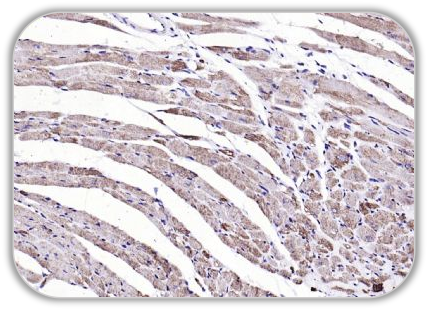

Anti-Desmin antibody (bs-33858R)

IHC Mouse Heart